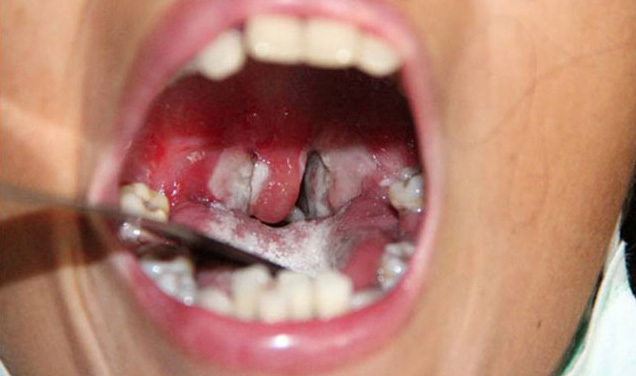

Biểu hiện bệnh có thể từ nhẹ đến nặng, thường có giả mạc màu trắng ở tuyến hạnh nhân, hầu họng, thanh quản, mũi, có thể xuất hiện ở da, các màng niêm mạc khác như kết mạc mắt hoặc bộ phận sinh dục, trường hợp nặng có thể gây biến chứng và tử vong.